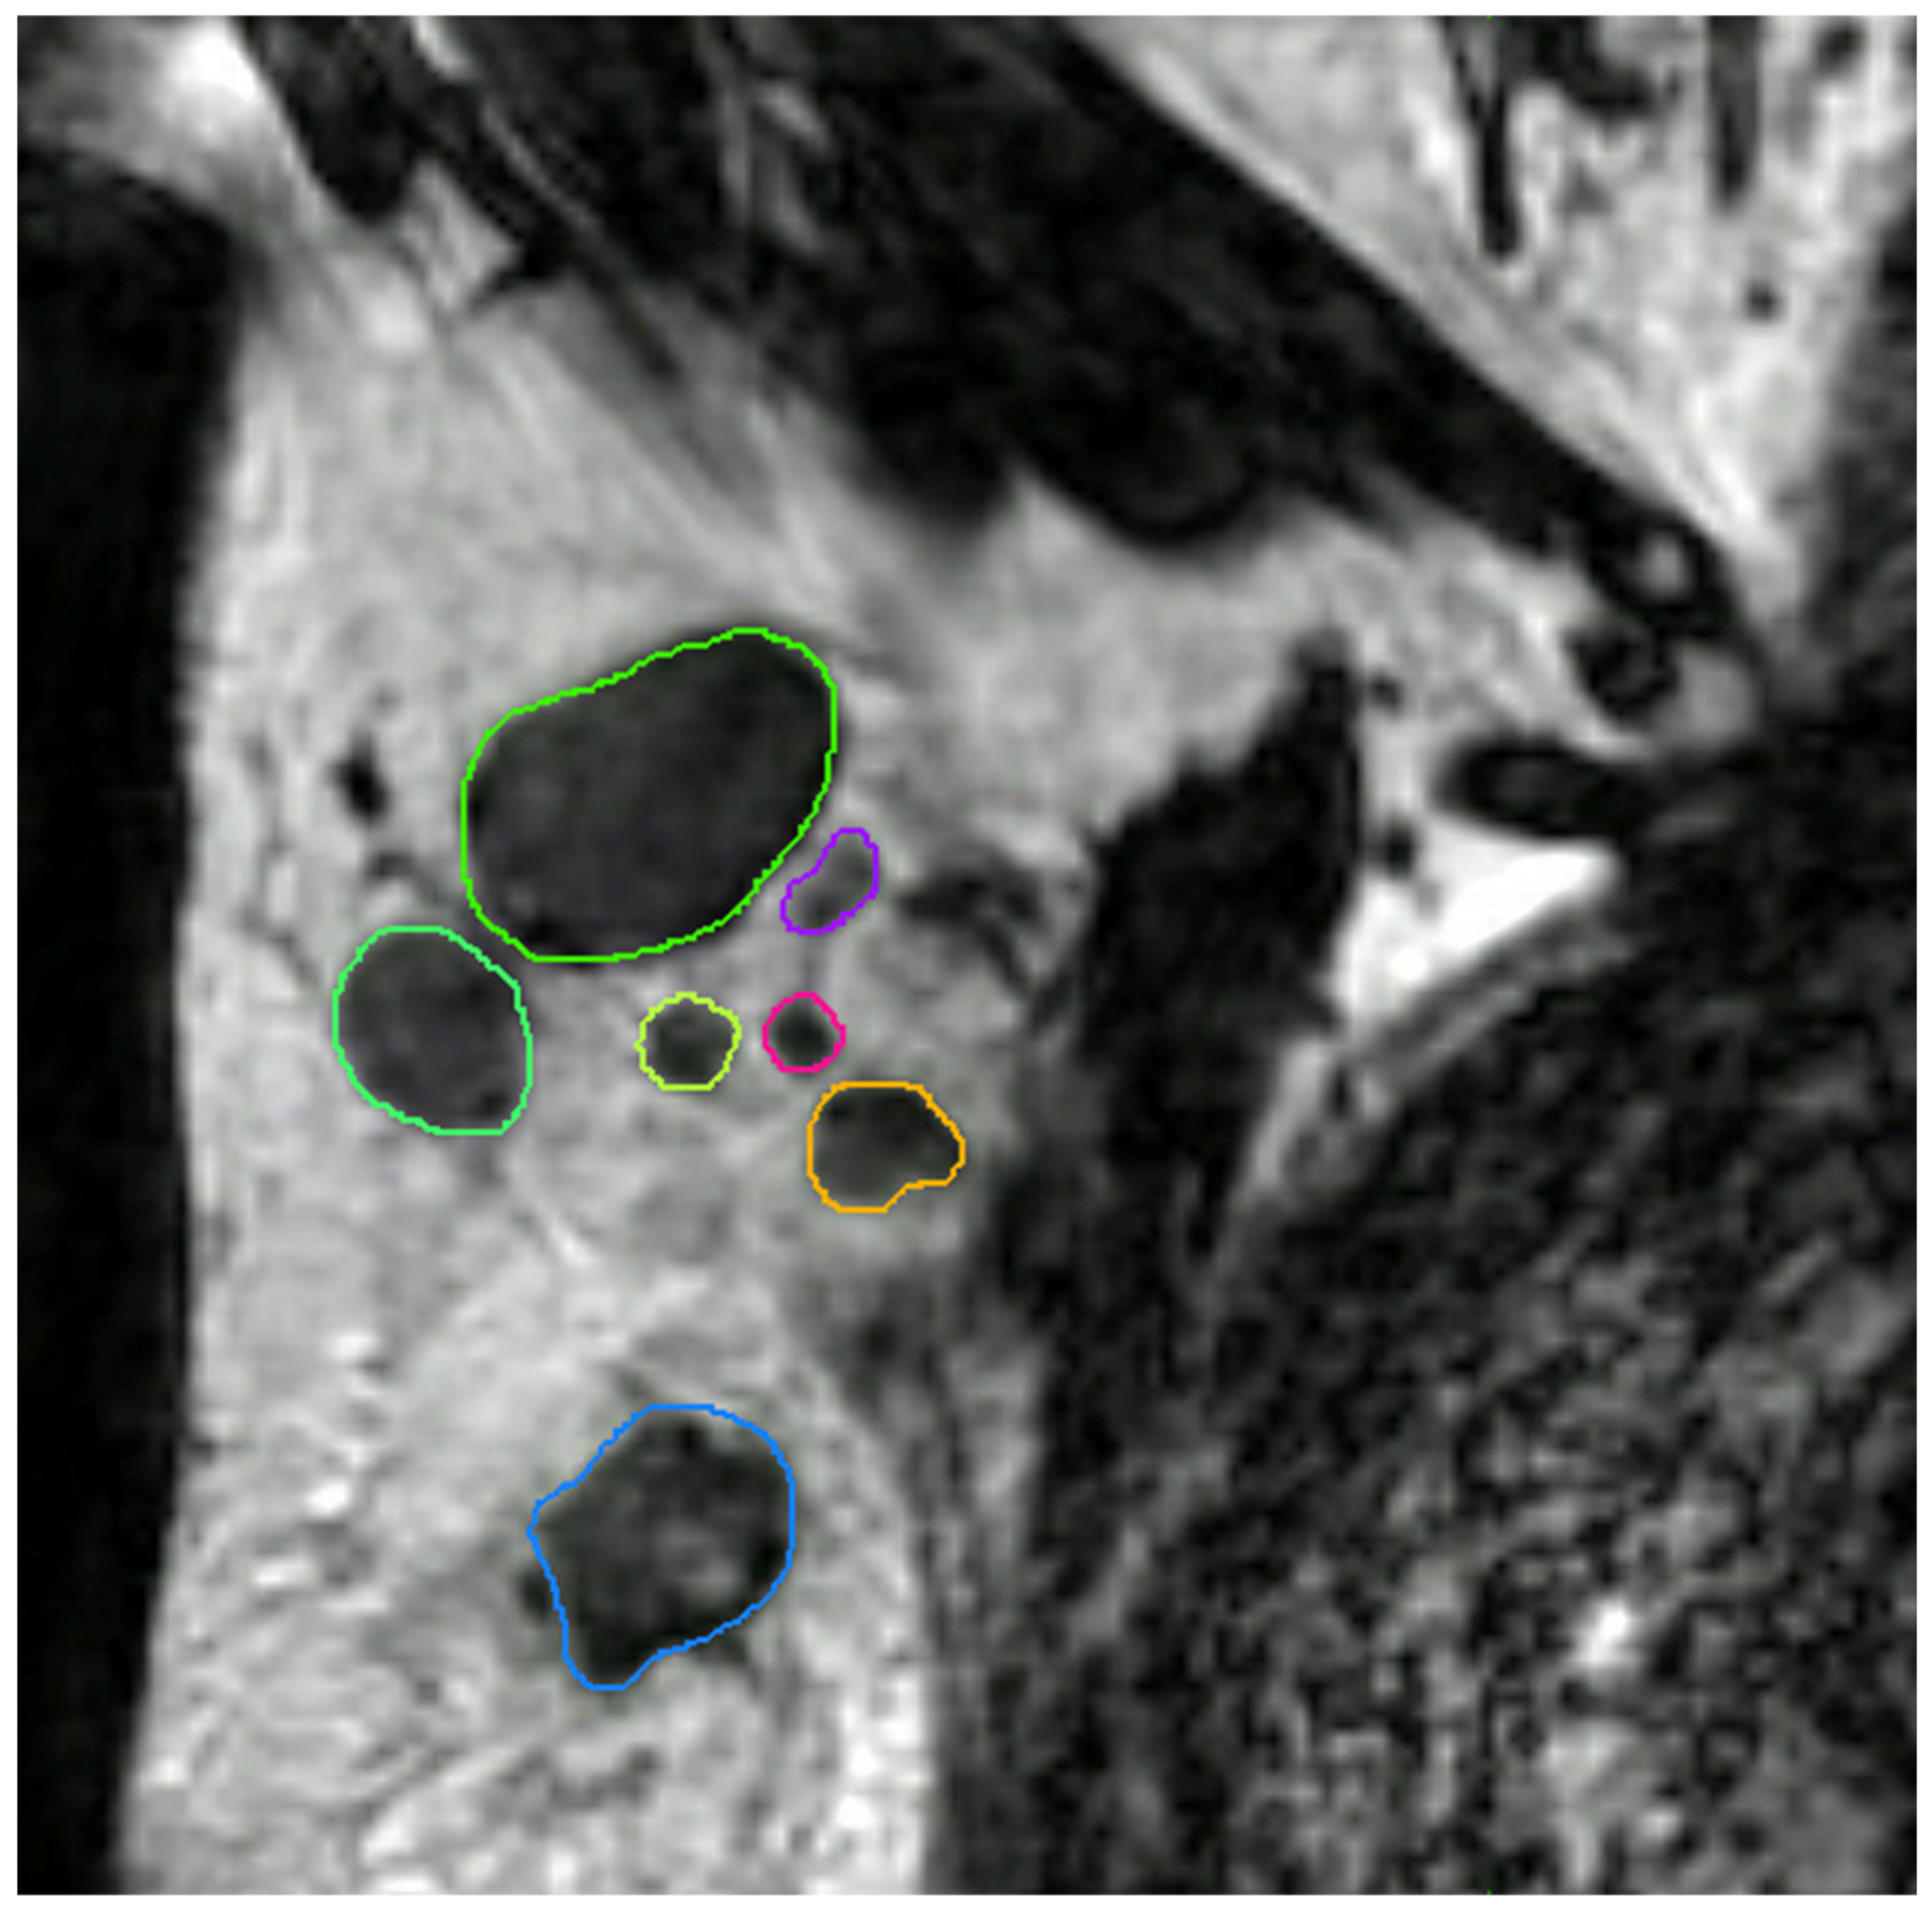

4.4. MRI Lymph Node Delineation

4.5. MRI Preprocessing and Feature Extraction